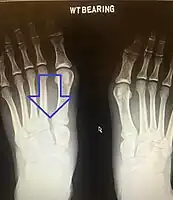

An X-ray of a Lisfranc injury showing widening between the 1st and 2nd metatarsal base.

In a high energy injury to the midfoot, such as a fall from a height or a motor vehicle accident, the diagnosis of a Lisfranc injury should, in theory at least, pose less of a challenge. There will be deformity of the midfoot and X-ray abnormalities should be obvious. Further, the nature of the injury will create heightened clinical suspicion and there may even be disruption of the overlying skin and compromise of the blood supply. Typical X-ray findings would include a gap between the base of the first and second toes.[10] The diagnosis becomes more challenging in the case of low energy incidents, such as might occur with a twisting injury on the racquetball court, or when an American Football lineman is forced back upon a foot that is already in a fully plantar flexed position. Then, there may only be complaint of inability to bear weight and some mild swelling of the forefoot or midfoot. Bruising of the arch has been described as diagnostic in these circumstances but may well be absent.[11] Typically, conventional radiography of the foot is utilized with standard non-weight bearing views, supplemented by weight bearing views which may demonstrate widening of the interval between the first and second toes, if the initial views fail to show abnormality. Unfortunately, radiographs in such circumstances have a sensitivity of 50% when non-weight bearing and 85% when weight bearing, meaning that they will appear normal in 15% of cases where a Lisfranc injury actually exists.[12] In the case of apparently normal x-rays, if clinical suspicion remains, advanced imaging such as magnetic resonance imaging (MRI) or computed tomography (CT scan) is a logical next step.[13]